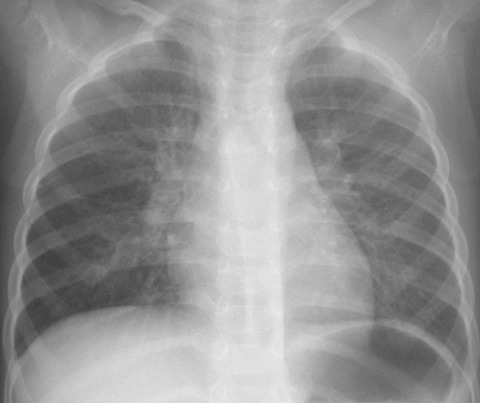

30代、高熱続き4日目酸素飽和度88%(COVID-19中等症)